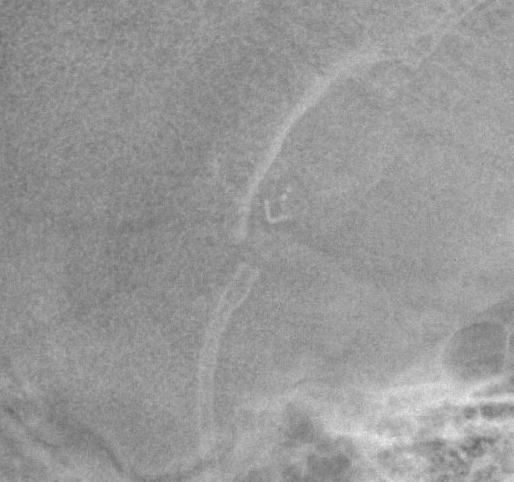

Spitz Holter

Spitz-Holter valves are non-programmable csf shunt valves introduced in 1956.